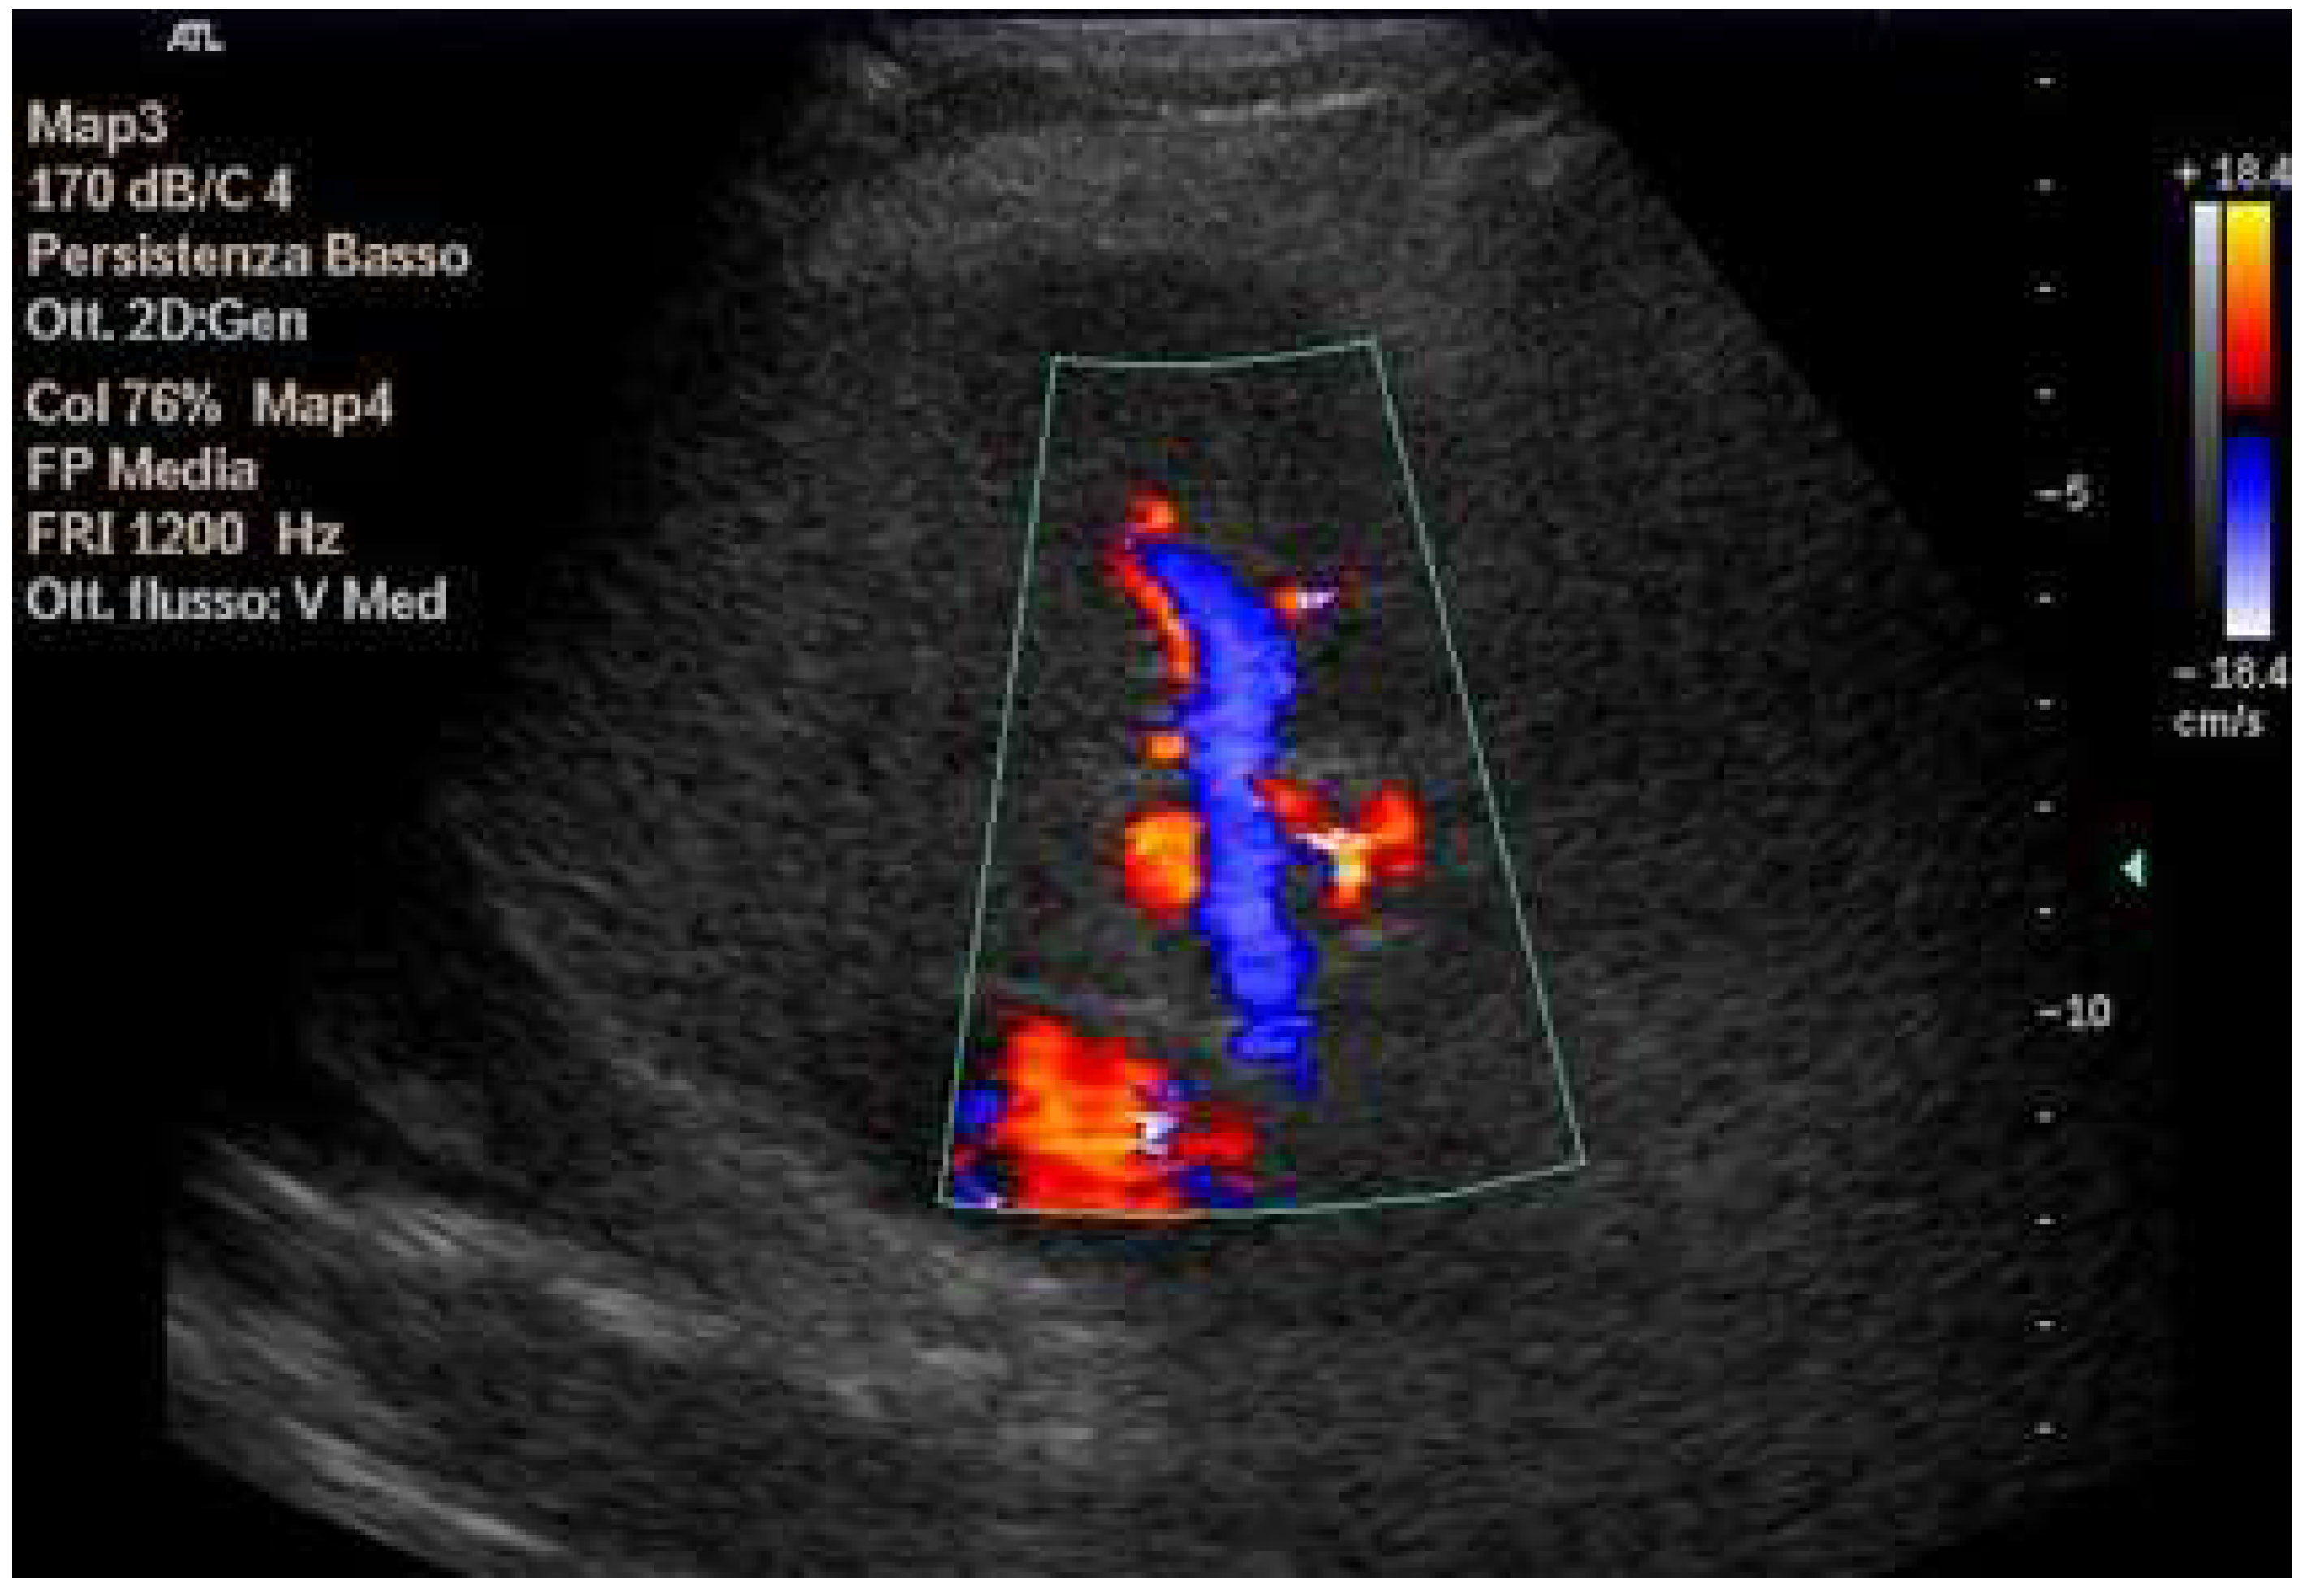

Doppler patterns in Fontan patients resemble those observed in chronic liver disease, including reduced portal flow velocity (mean flow velocity < 14 cm/s) [56]. The Fontan procedure inevitably alters hepatic venous waveforms on Doppler US (Figure 10, Figure 11, Figure 12 and Figure 13). Inverted portal flow has a specificity of 100% for diagnosing PHTN [57] (Figure 12). The hepatopetal phase pattern in the hepatic vein differs between patients with total cavo-pulmonary anastomosis (including both lateral tunnels and extracardiac conduits) and those with atrio–pulmonary connection [58,59,60]. In atrio–pulmonary connection, hepatopetal flow is preserved (Figure 10), reflecting the exclusion of atrial contribution to venous circulation, whereas in total cavo-pulmonary anastomosis, flow reversal (Figure 11) occurs only during early expiration. Similarly to congestive heart failure, hepatic veins and the IVC are dilated, with abnormally increased hepatic vein pulsatility, regardless of the anastomosis technique [54,61,62]. The loss of the normal three-phase Doppler pattern in hepatic veins is universal following bi-cavo-pulmonary surgery due to the absence of atrial contraction. The presence of a monophasic pattern indicates advanced liver injury [63].

Inverted portal flow in cavo-pulmonary anastomosis.

Figure 13.

Changes in hepatic vascularization in a patient with FALD. The middle hepatic vein is patent, although irregular, within the context of the parenchymal nodularity.